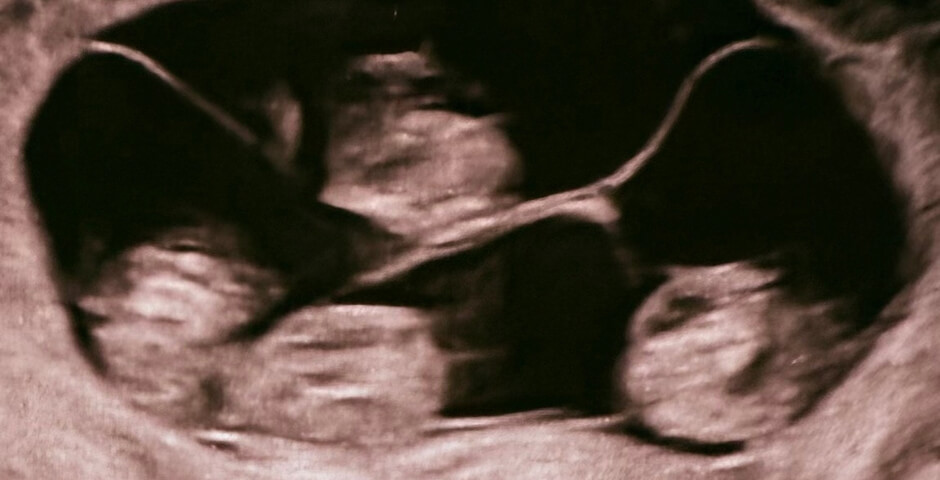

Специалисты разъяснили, что такое происходит 1 раз в 15,5 миллиона родов. Все четверо — неотличимые девочки-близнецы.

Вес новорожденных от 1 360 до 1 640 граммов, а рост — от 37 до 41 сантиметра. Сейчас они находятся под наблюдением медиков.

Всего в мире насчитывается около 15 идентичных четверняшек, 10 из них — девочки.